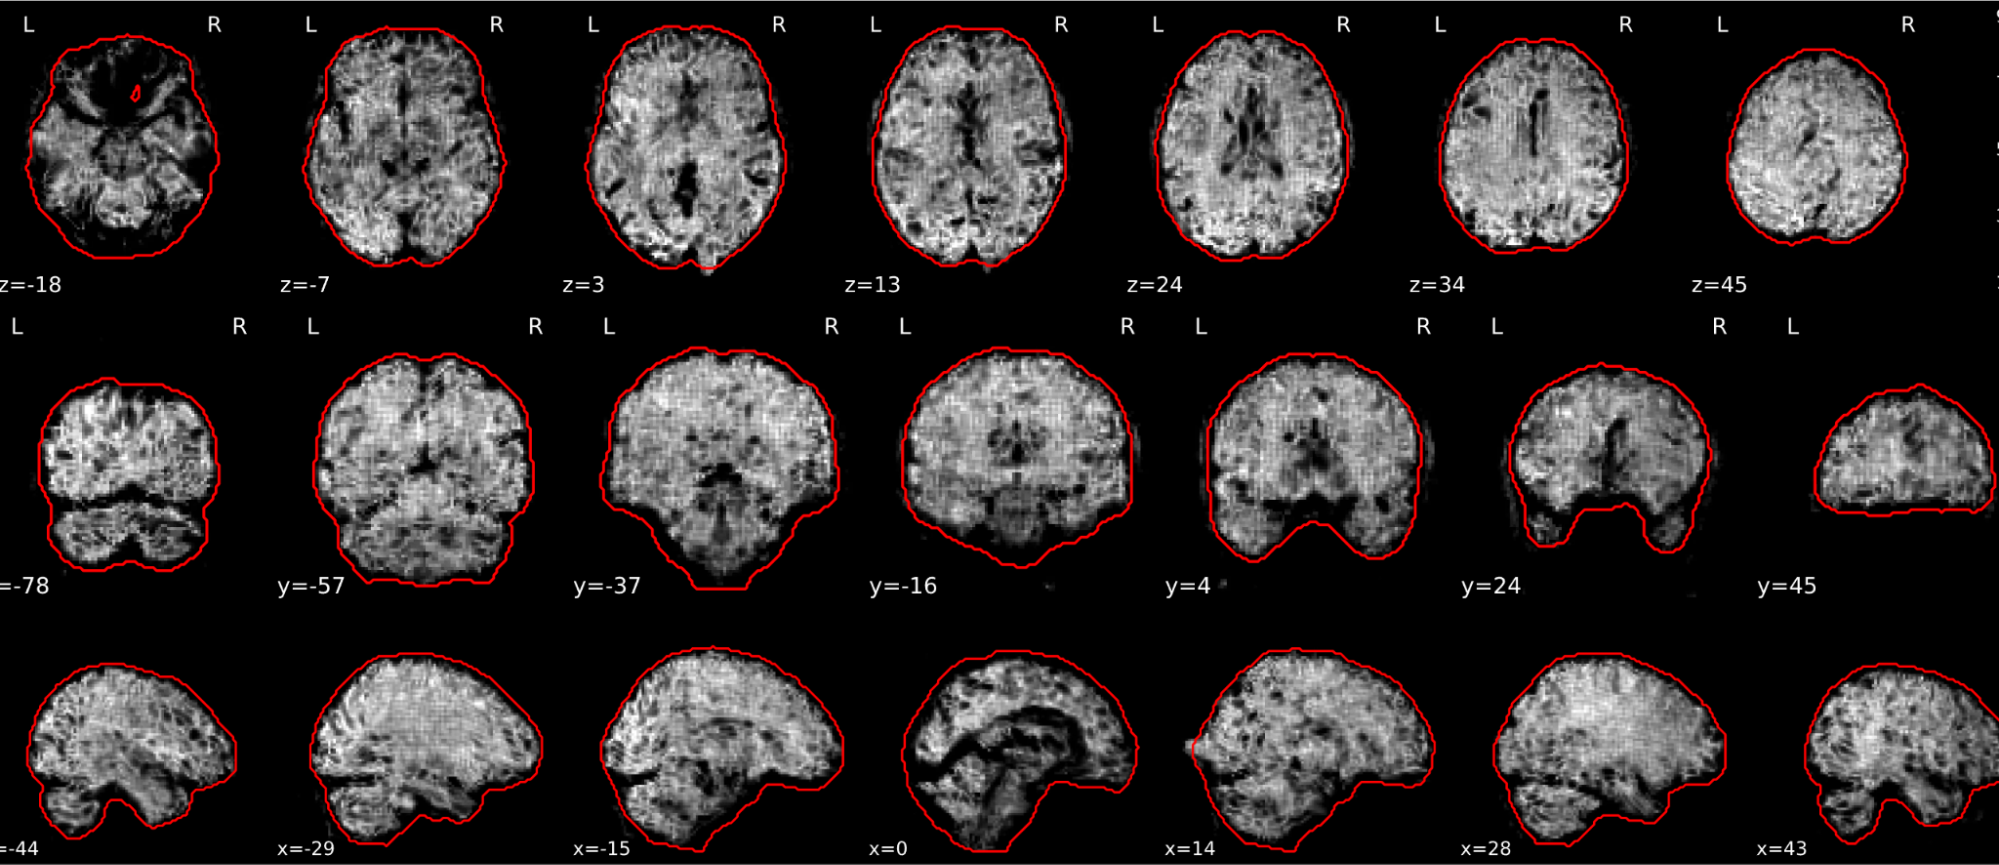

EPI tSNR

In the signal to noise ratio images of the resting state image the desired signal is compared to the amount of background noise. It is important to check all the views (sagittal, coronal, axial) because some artefacts (e.g., stripes) may be evident only in one particular view.

Example of a good subject

- Signal to noise is symmetrically distributed and there is no signal distortion

Example of a bad subject

- Asymmetry

- Potential signal distortion (might represent an artefact)

- Signal drop-out

- Stripes artefact

Clear large artefact (e.g., zebra stripes in example 1) are worth the exclusion of the subject. If you are unsure, check the other quality metrics for that subject to decide whether they should be excluded.

Summary

| good | bad |

|---|---|

| Symmetrical distribution of noise and signal | Asymmetry |

| No disruptions of the signal (no “black patches”) |

Potential signal disruptions (could be related to artefacts) |

| No stripes (sign of high motion) |

Signal drop |

| Stripe artefacts (“zebra” stripes due to motion) |